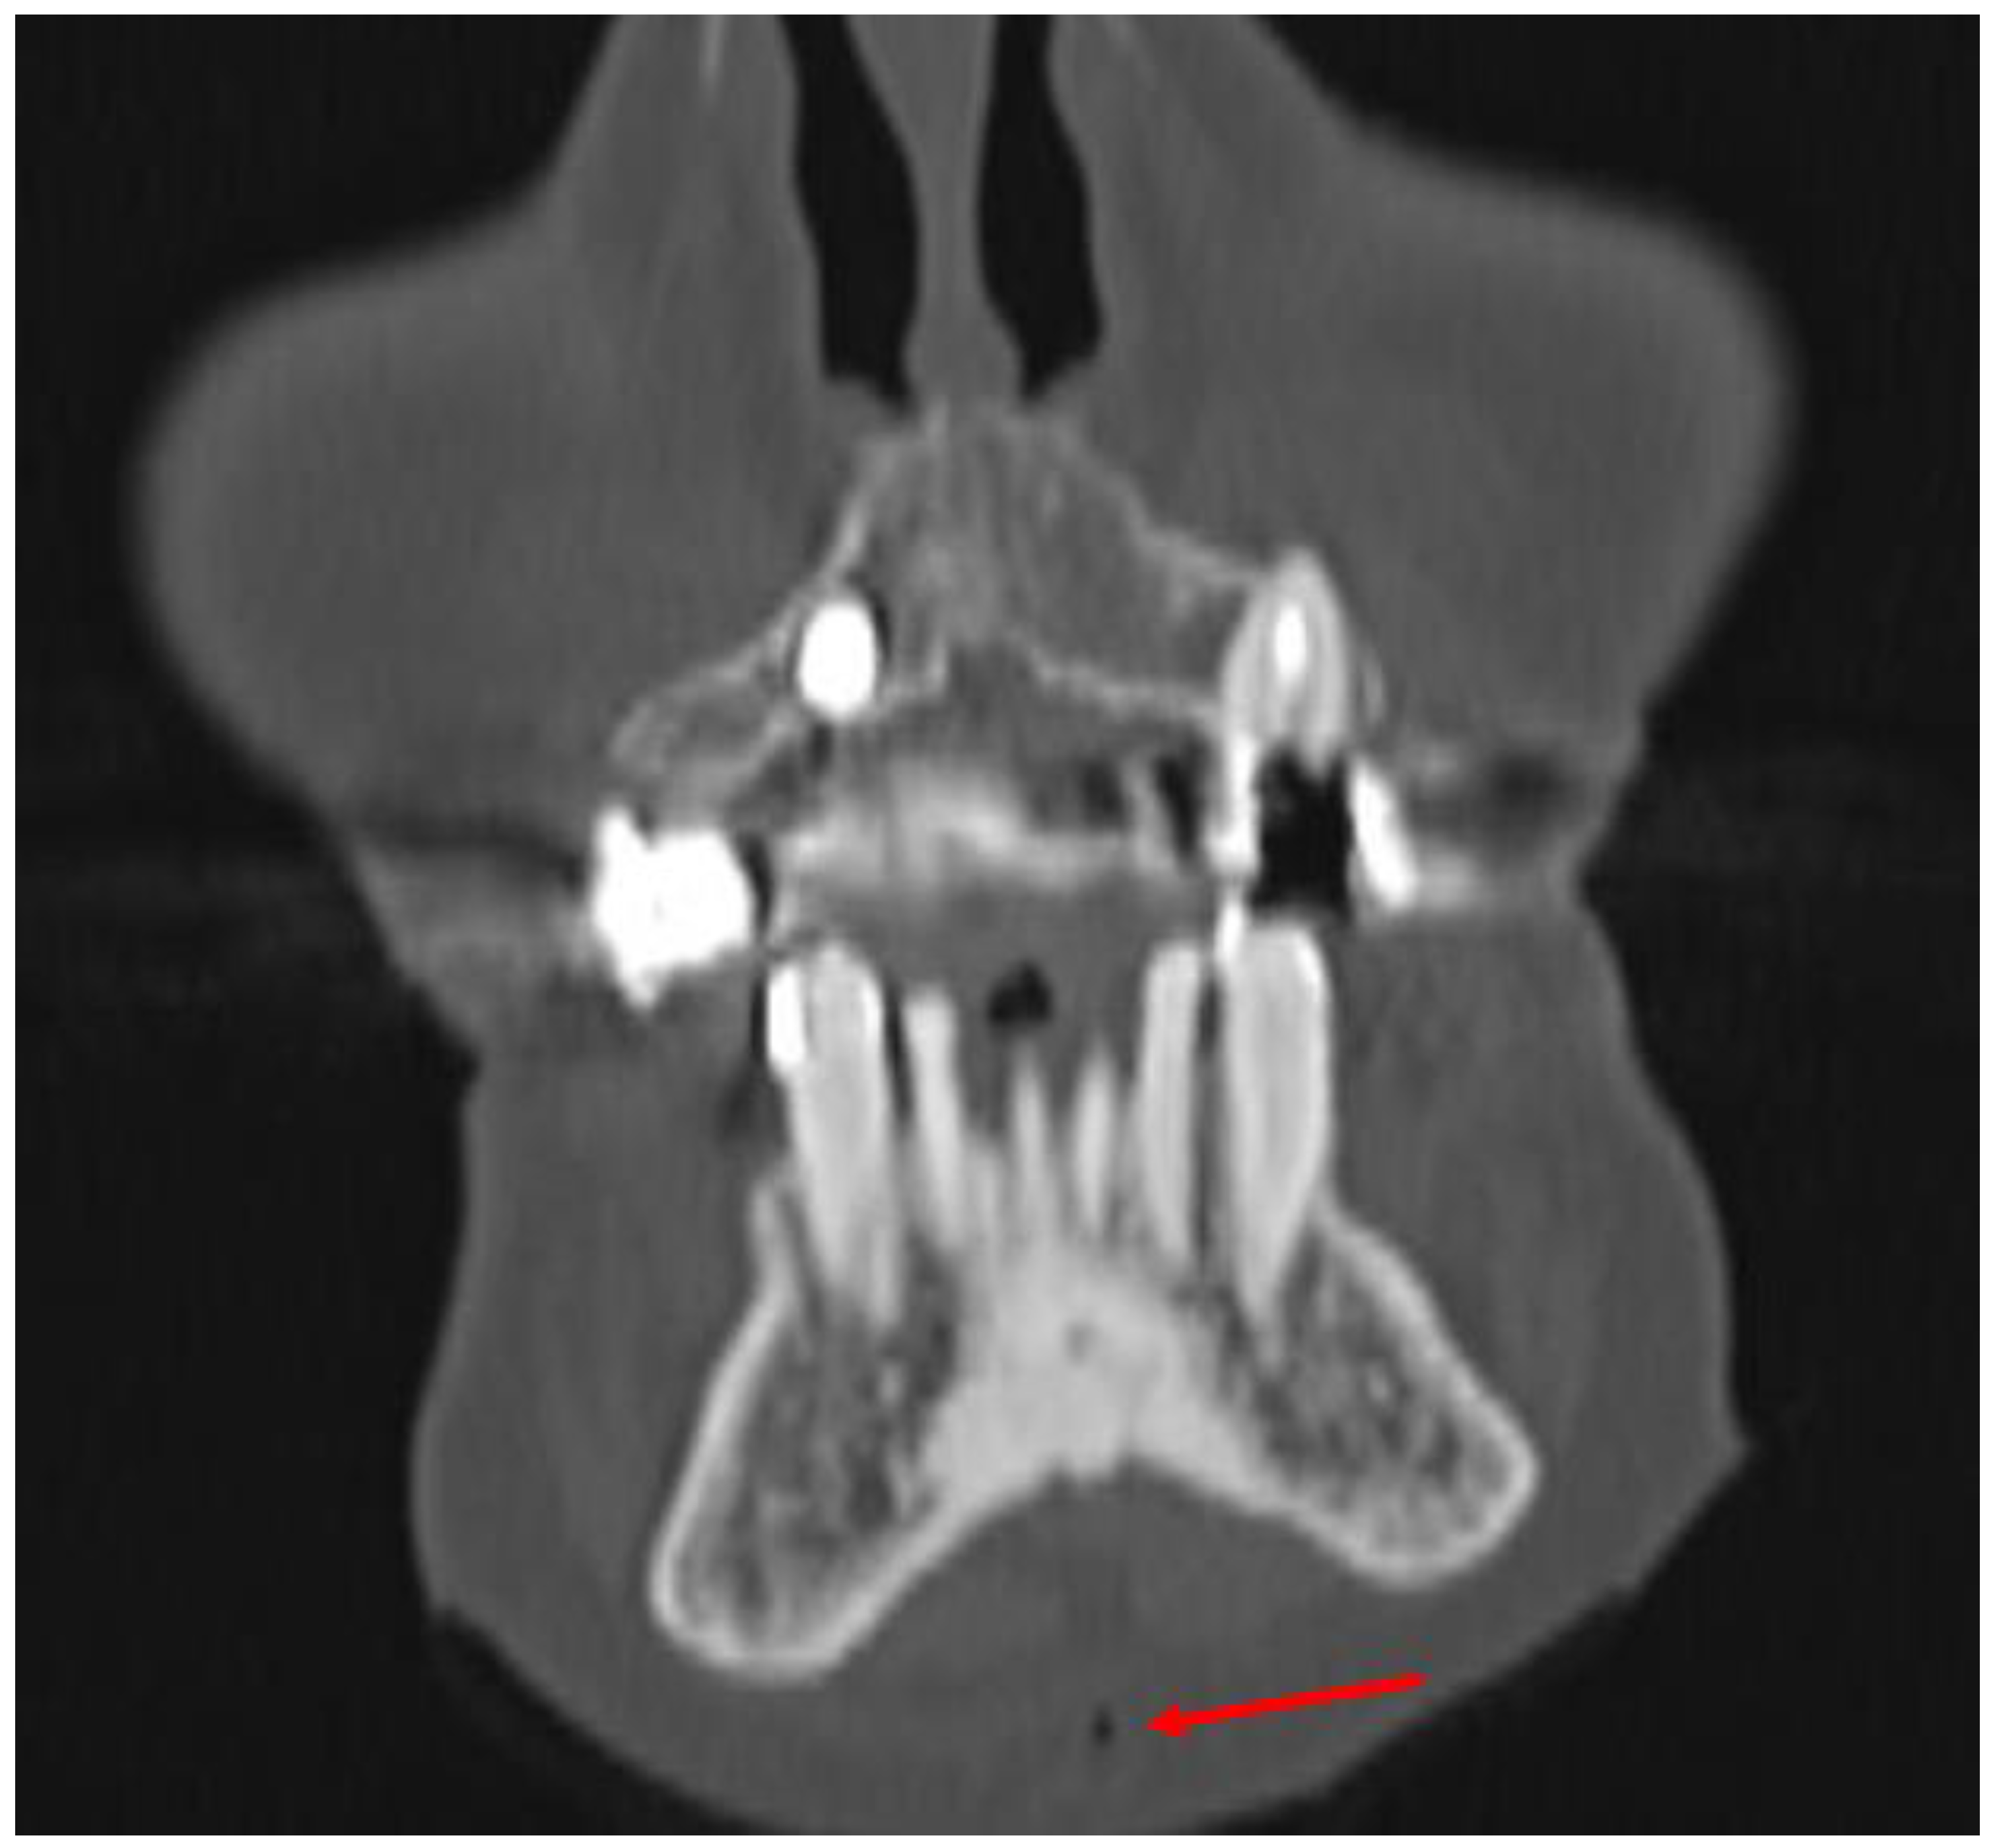

3.1. Case 1